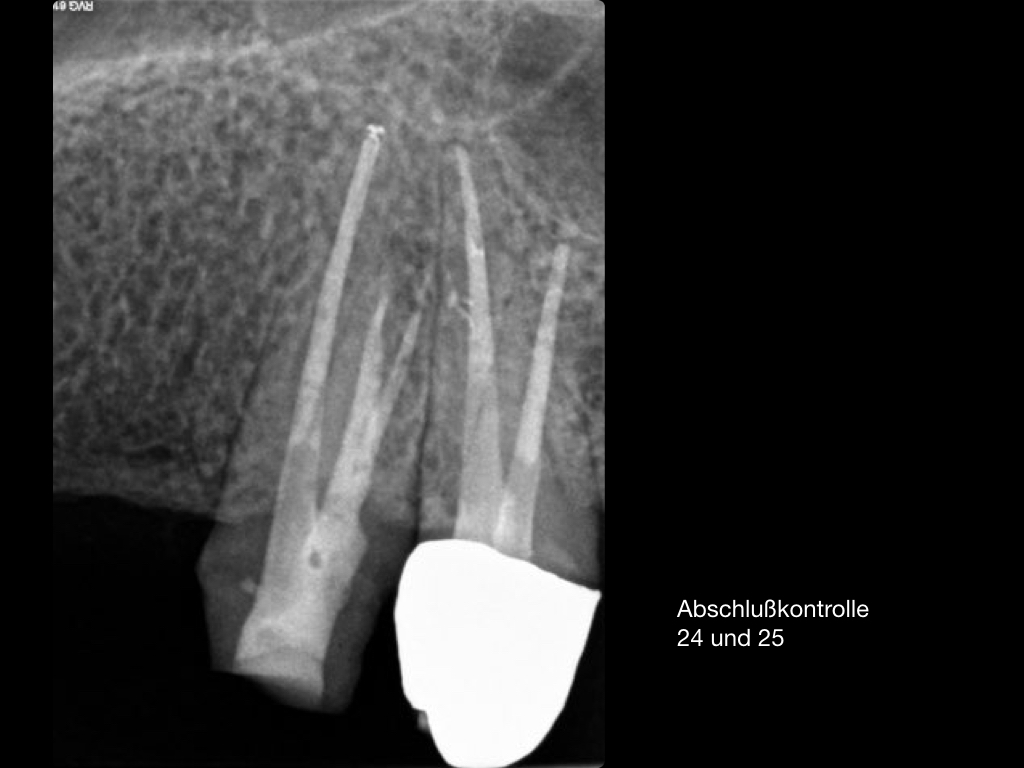

Es ist zu sehen … (2)